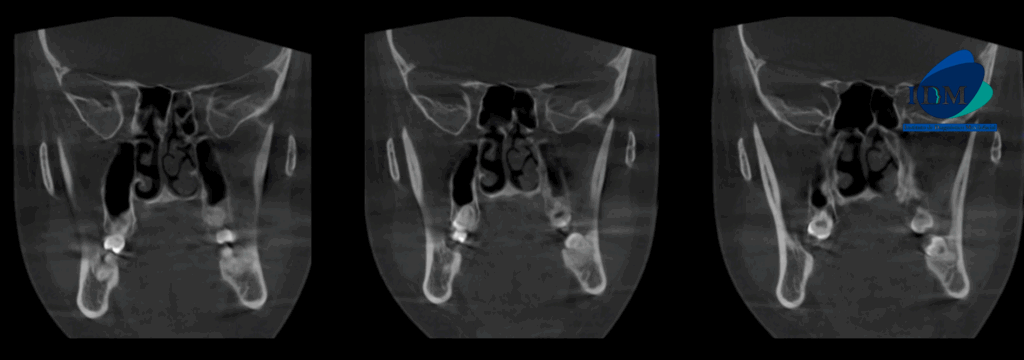

A la evaluación de la tomografía computarizada se puede observar el aumento de la longitud cefalo caudal de la apófisis coronoides bilateral que se extiende superior al borde del arco cigomático.

CORTES CORONALES